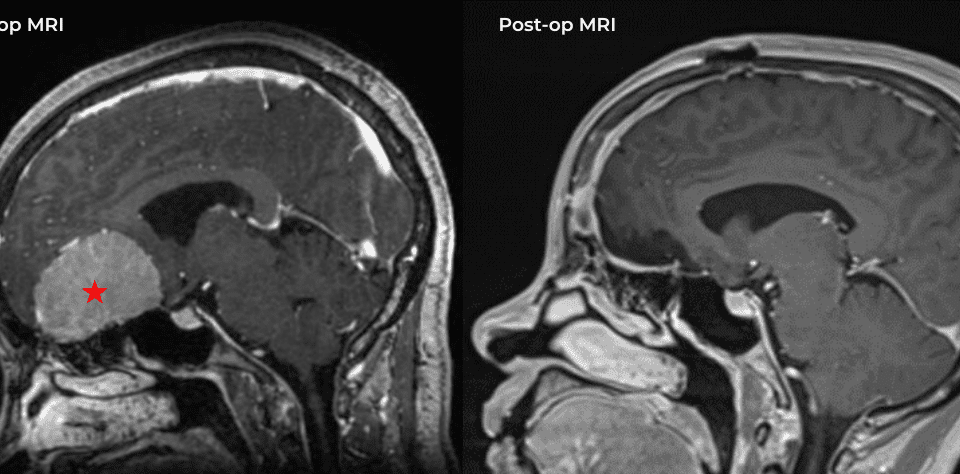

This is a 49-year-old otherwise healthy female who presented with bifrontal and retro-orbital headaches, behavioral changes, and forgetfulness. Symptoms have been progressively worsening over the past […]